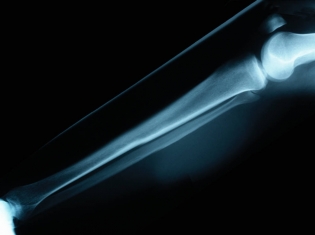

(RxWiki News) Joint replacement surgery might seem fairly routine in today's on-demand health care system. The added risk for blood clots in the lungs following knee operations can add an extra complication.

A pulmonary embolism happens when a blood clot forms in the veins, usually in the legs or other limbs, then becomes free and travels to the lungs, possibly cause serious complications, including death.

Researchers evaluated 37,223 knee replacement patients who had surgery between 1997 and 2007. They then searched for evidence of a pulmonary embolism in the 90-day period immediately following surgery.

They found that 441 patients, about 1.2 percent, were hospitalized for blood clots during that 90-day period after surgery. A review of patients records revealed that risk factors including older age, history of heart disease or a previous blood clot or an increased number of additional medical conditions added to the blood clot risk.